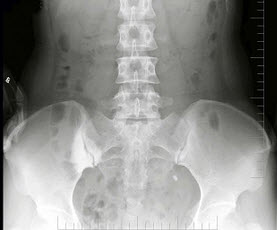

C.有空洞的外周型肺癌多为腺癌

157、单项选择题

女,60岁,大腿后侧痛,下腰痛1月余,结合图像,最可能的诊断是()

A.类风湿关节炎

B.强直性脊柱炎

C.牛皮癣性关节炎

D.Reiter综合征

E.痛风性关节炎